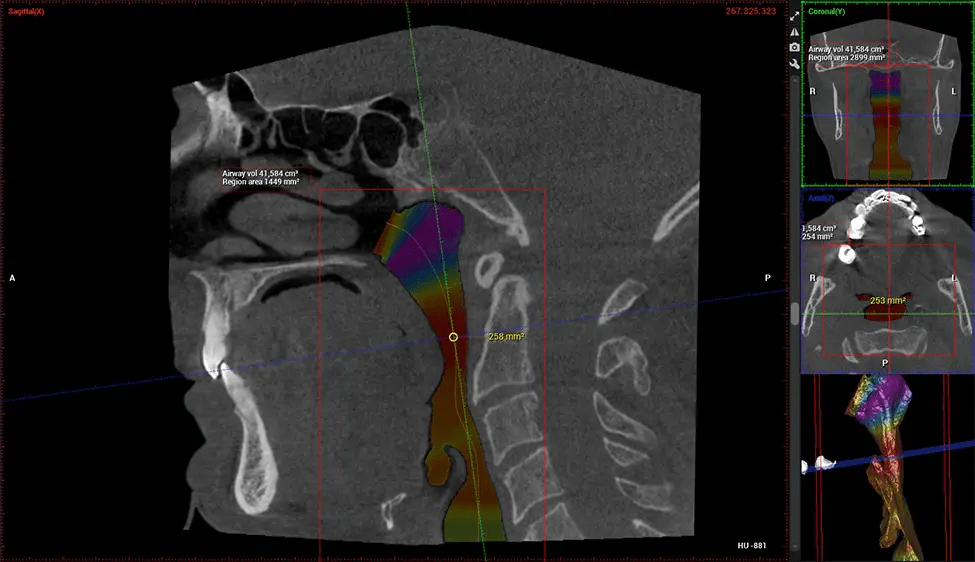

ENT Physician Diagnosing obstructive sleep apnea (OSA) and evaluating sinus and nasal cavity anatomy. Visualizes the entire pharyngeal airway to measure volume, pinpoint constrictions, and plan corrective surgery if needed.

Screening and treating patients at risk for OSA.

Provides detailed 3D imaging for airway analysis, helping to create and adjust oral appliances and facilitate effective referrals to medical doctors.